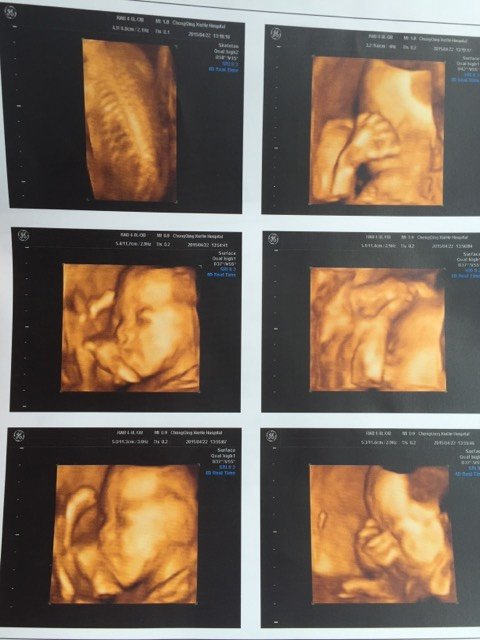

四维和系统b超一起归来。为了检查清楚宝宝的各种五官和内脏,为了让他翻个身动一下,高抬腿爬了半小时楼梯,把我累的半死。因为怀孕初期吃过消炎药,一直担心宝宝出问题,结果检查出来一切正常,差点激动的哭了。宝宝其实比我们想得要坚强!